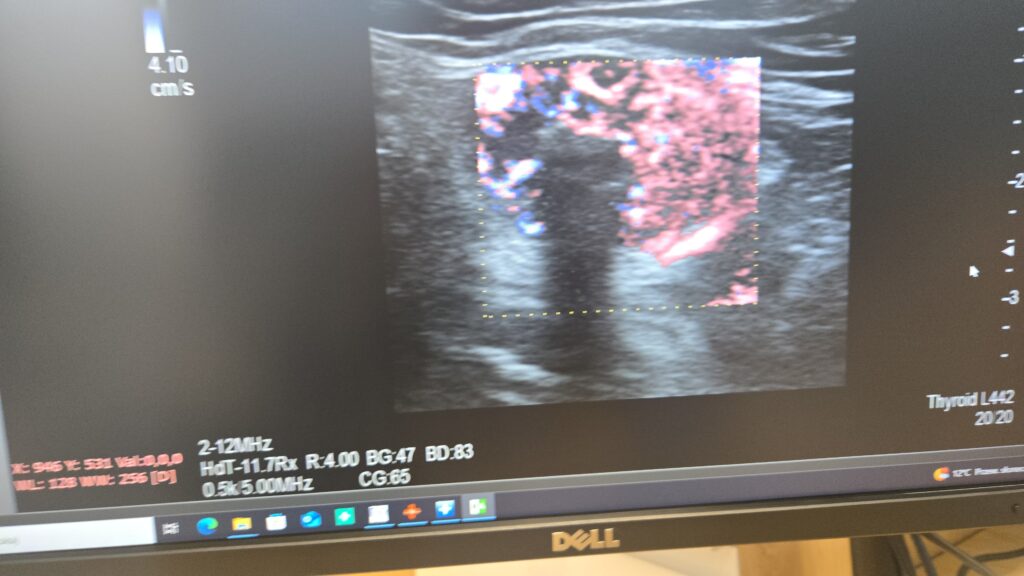

Podczas wizyty pacjent zostaje poproszony o położenie się na leżance i odchylenie głowy. Lekarz przykłada głowicę do skóry szyi, wcześniej pokrytej żelem, i analizuje obraz wyświetlany na monitorze. Cała procedura trwa kilkanaście minut i nie powoduje żadnego dyskomfortu.

W trakcie oceny lekarz analizuje:

- unaczynienie tarczycy,